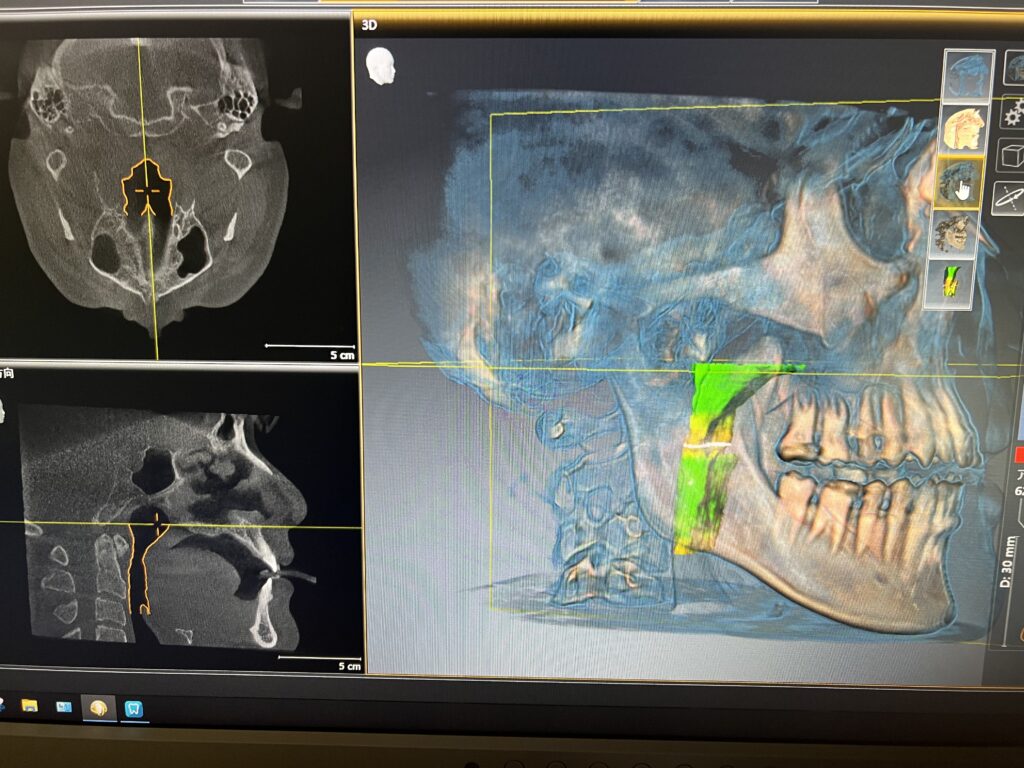

気道解析

CTの撮影範囲を広げることによって咽頭の方まで見ることが可能となり、そこから気道の広さや形などを確認出来ます。

これによって、現代病として突然死などが問題になっている睡眠時無呼吸症候群(←押して頂くと睡眠時無呼吸症候群のページへ)の可能性を見たり、睡眠時無呼吸用の口腔内装置を入れて気道がどう変わるかなどを確認することが可能です。

このように気道の状態を3次元的に見やすくして、どこが狭いかなども把握できます😲